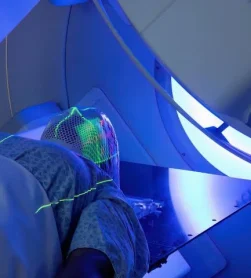

لیزر کم توان

کاهش درد و تسریع ترمیم زخم